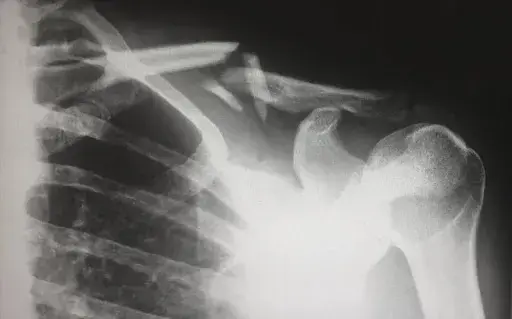

From the humble stethoscope to the X-ray, technological innovation in medicine has been directly responsible for saving lives, as well as improving the quality of life for hundreds of thousands of people every year. Today we are going to examine how our species’ technological progress has impacted the world of nursing.